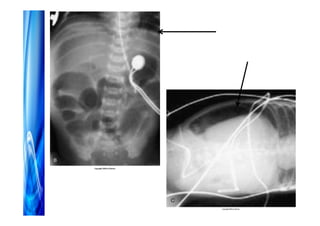

Acesso venoso

• Periférico

• Central PICC